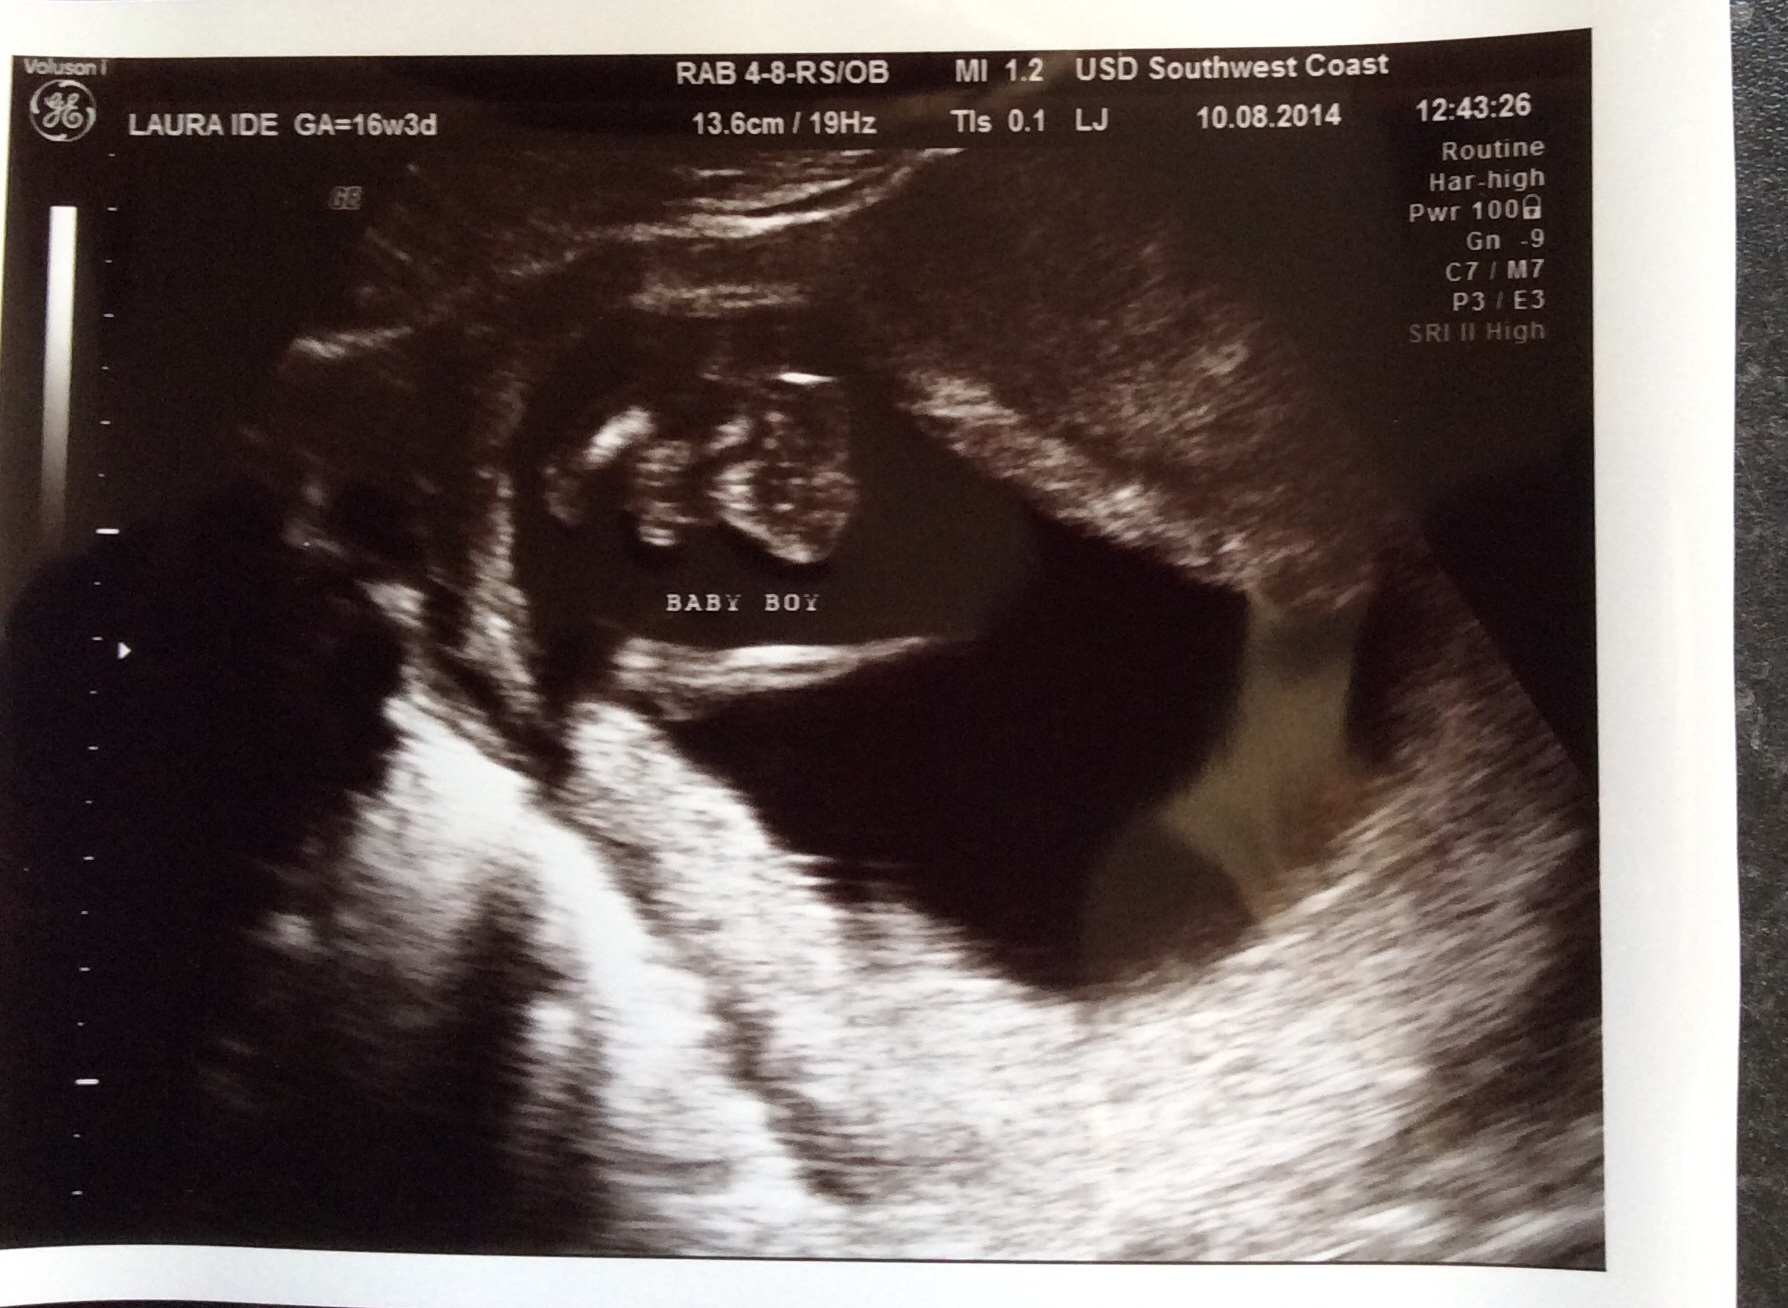

Been told boy but potty shot 16+3 I'm not so sure??

When we got called back in she had another look but still struggled she was saying I'm going to have to get you back in, then she got a picture and said boy! We have 3 photos all together?

I don't think it looks anything like a boy but I am by no means an expert! With our son his 16w gender scan was a clear turtle it was no mistakable at all so I kind of knew what I was looking for!

Through the whole scan me and hubby didn't catch site of any boy bits and were so shocked when she said boy! I just wondered what you guys thought? If it is then that's fine and I will except that I'm having boy number 5 but just don't want to think I'm having a boy choose his name and it be a girl, I need to know so I can bond with the baby!

I suffered bad GD last time and don't want that this time that's partly why we gave had this scan! At the end of the scan the lady said baby was very difficult and I think you should just make sure it's defiantly a boy when you go to your 20 weeks scan. I thought that was a lil odd as never had a tech say that to me before!

Anyways this is the scan potty shoots! The first one she said was boy